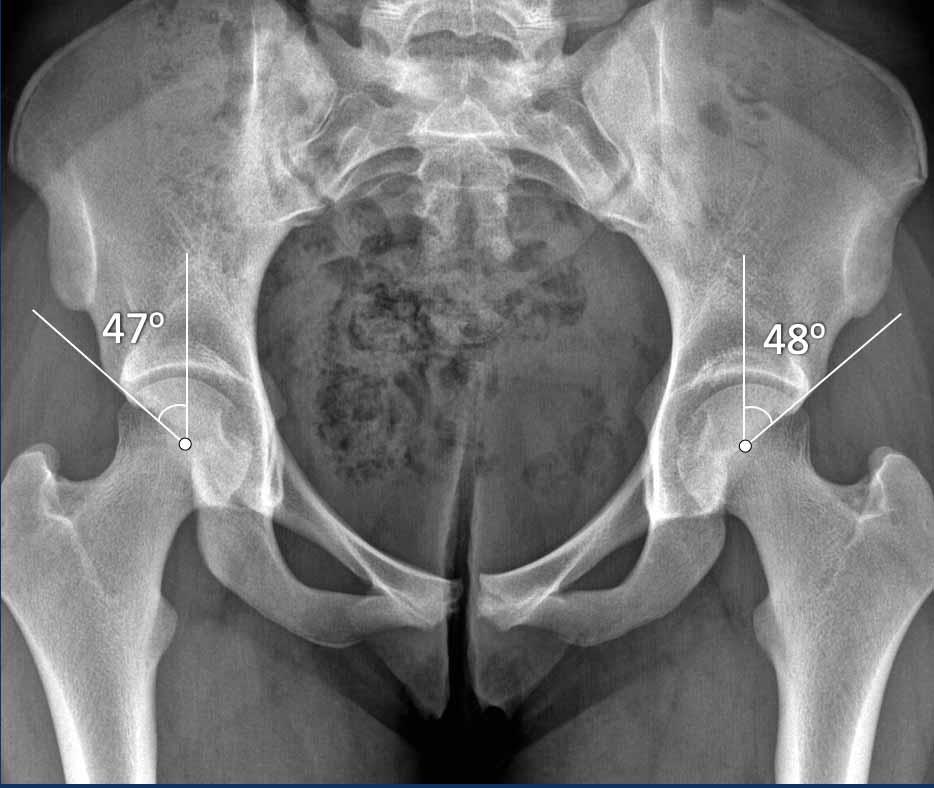

W-CEA

W-CEA là góc giữa đường thẳng đứng đi qua tâm chỏm xương đùi và đường thẳng đến bờ ngoài của vòm ổ cối, đây là vùng chịu lực và đặc của phần trên ổ cối.

Góc này đại diện cho độ che phủ phần trên-trước, có liên quan nhiều hơn đến FAI.

L-CEA

L-CEA là góc trung tâm-cạnh bên, được đo đến bờ ổ cối ngoài xa và đại diện cho độ che phủ trên-ngoài.

Đôi khi các phép đo này trùng nhau.

Kiểu kẹp gọng kìm đơn thuần hai bên (chỉ có hình chụp tư thế AP) với góc W-CEA tăng và dấu hiệu gai ngồi ở bệnh nhân nữ 16 tuổi, đến khám vì các triệu chứng liên quan đến khớp háng.